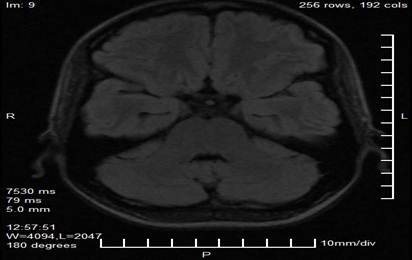

Los estudios complementarios incluyeron una resonancia magnética de cráneo con protocolo neurooftalmológico, la cual reveló una imagen nodular, lobulada y bien delimitada en proyección de la glándula pineal, con dimensiones de 29 mm × 28 mm × 27 mm. La lesión presentaba características de señal heterogénea, con áreas de hiperintensidad en secuencias T1 y T2 sugestivas de componente hemorrágico o vascular, y evidenciaba efecto compresivo sobre el tectummesencefálico y los colículos superiores. No se observaron signos de hidrocefalia obstructiva ni hipertensión intracraneal en los cortes obtenidos (Figuras 2 y 3).

Figura 3. Corte axial de resonancia magnética que demuestra la extensión de la lesión pineal y su relación anatómica con el tectummesencefálico y los colículos superiores (área sombreada).